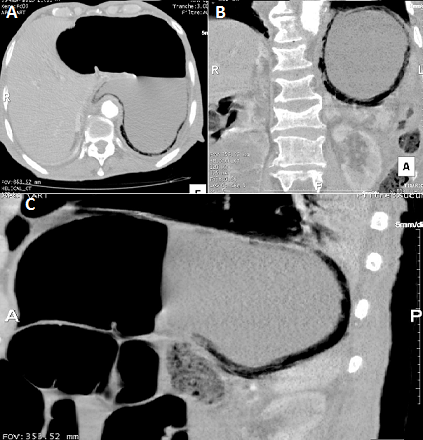

La gastrite emphysémateuse, caractérisée par la présence de gaz dans la paroi gastrique, est due à une infection par des germes « producteurs de gaz ». Son pronostic est sombre avec une mortalité très élevée, imposant un diagnostic et un traitement précoces. Le tableau clinique n'est pas spécifique. Le diagnostic est souvent radiologique. La chirurgie est indiquée en urgence en cas de nécrose, de perforation, de péritonite ou de détérioration rapide de l'état du patient sous traitement médical. Nous rapportons le cas d'un homme de 79 ans, aux antécédents de maladie d'alzheimer depuis 3ans, diabétique sous antidiabétiques oraux depuis 30 ans, qui s'est présenté aux urgences pour une douleur épigastrique évoluant depuis 48 heures. A l'examen, il présentait un état septique avec fièvre à 39,5°C et frissons avec tendance au collapsus. Il était polypnéique et il y avait une défense abdominale à l'étage sus-ombilical. Il existait une hyperleucocytose à 25 000/mm3, une CRP à 280 mg/l et une acidose métabolique. La tomodensitométrie abdominale (A, B, C) montrait du gaz dans la paroi gastrique et confirmait le diagnostic de gastrite emphysémateuse. Les axes vasculaires digestifs, en particulier le tronc coeliaque, étaient perméables. Il n'y avait pas d'aéorportie. Une antibiothérapie à large spectre couvrant les germes gram négatifs et les anaérobes a été démarrée, et une préparation du patient pour une chirurgie en urgence a été entamée mais le patient décédait d'une défaillance multiviscérale avec un syndrome de détresse respiratoire aigu, une heure après la réalisation du scanner abdominal.